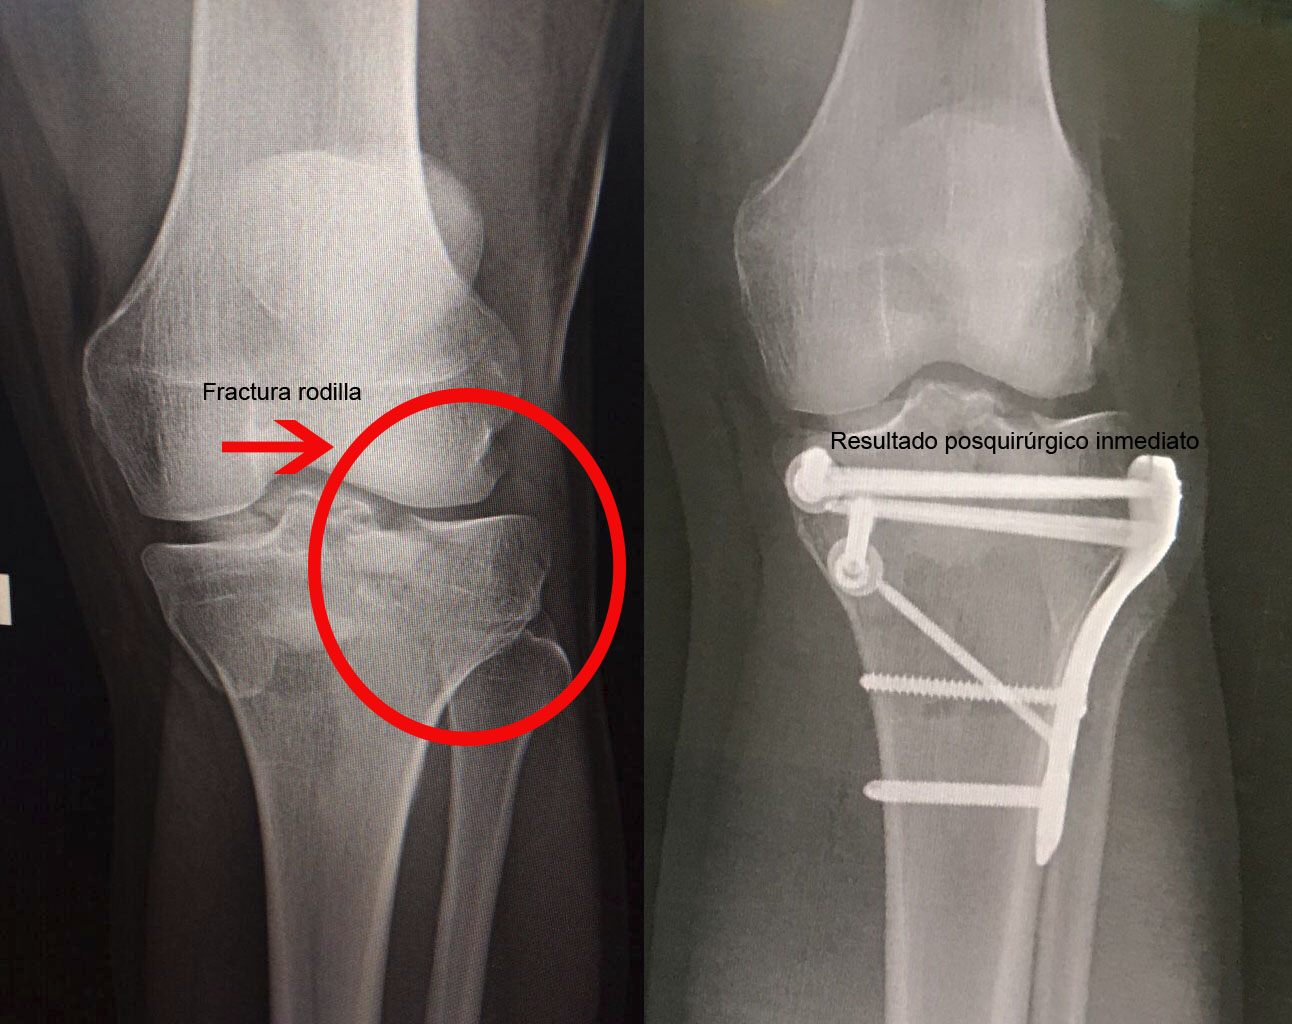

Una fractura ósea es la ruptura de un hueso, la cual puede presentarse por diversas causas y su tratamiento dependerá de la magnitud, sitio anatómico y de las enfermedades concomitantes. Algunas pueden manejarse de forma conservadora con solo inmovilización y hay otras que requieren de un tratamiento quirúrgico. A continuación, podrá ver algunos casos quirúrgicos, dando clic a la zona del cuerpo afectada.